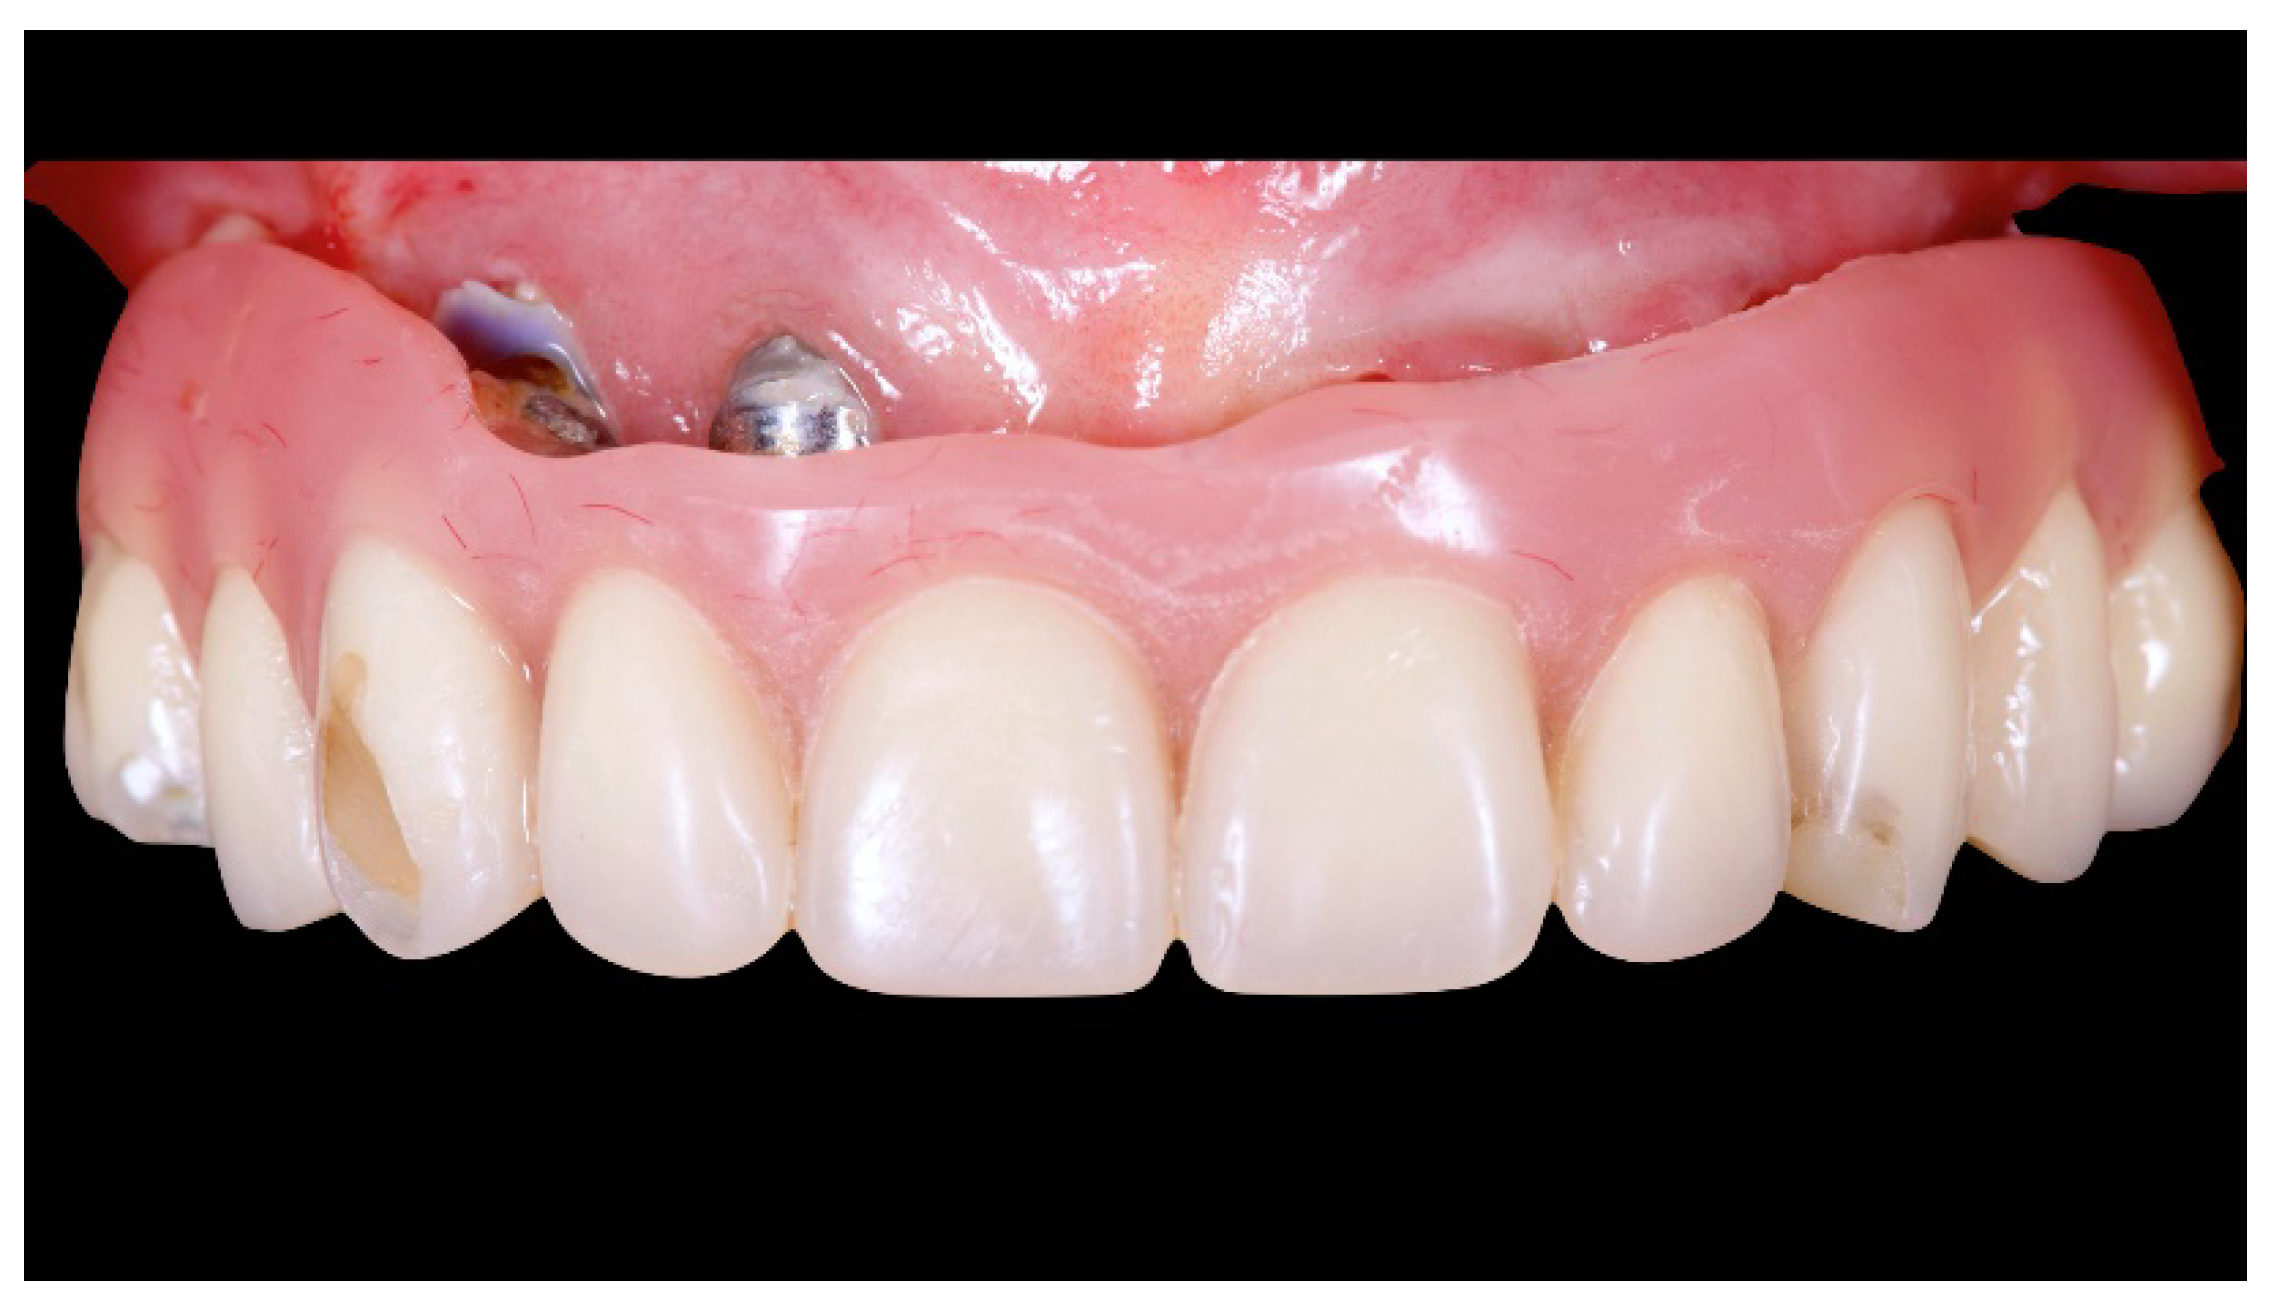

A partially edentulous 78-year-old woman with a complete screw-retained implant-support hybrid prosthesis (Figure 1) in the upper jaw and natural dentition in the lower jaw was referred to a private center in Rome, Italy, due to several continuous breakages of the prosthetic part of the implant-supported rehabilitation. After a preliminary interview, the patient stated that the implant treatment was finished two years before, but she had never been comfortable with this prosthesis (Figure 2). Relevant symptoms were phonetic difficulties, inability to maintain hygiene, and repeated breakages, leading to functional and esthetic issues (Figure 3). After that, the patient’s medical history was collected, and preoperative photographs, radiographs, periodontal screening results, and model casts were obtained for initial evaluation (Figure 4). During the clinical examination, the actual prosthesis was unscrewed, due to teeth detachments, and replaced with the old temporary prosthesis delivered by the patient. Both existing prostheses were evaluated and judged inaccurate, with particular attention to the fit of the prosthesis, the vertical dimension of occlusion, phonetics, facial support, and lip position. All the possible treatment options were then discussed and evaluated together with the patient. The main concerns of maintaining the previously placed implants were some exposed threads and the troubling disparallelism that makes the prosthetic treatment difficult, increasing the risk for biological complications and technical complications, respectively (Figure 5). Nevertheless, the patient refused a complete removable denture, so that implant removal would lead to placement of new implants, in combination with guided bone reconstruction and soft tissue management. This treatment plan may have the risks of implant failure and increased patient morbidity (Table 1 and Table 2). An implant-supported fixed dental prosthesis was initially excluded due to the implant’s disparallelism. Hence, a maxillary implant-supported overdenture was initially considered quite possibly the best therapeutic option.

Figure 1.

Picture of the patient’s work and initial situation.